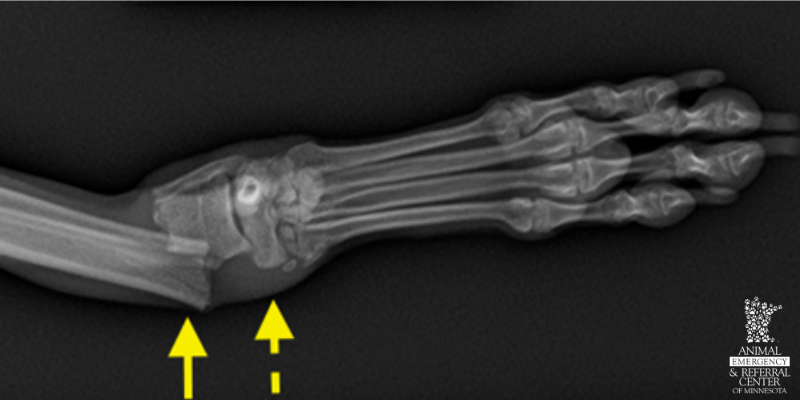

Front limb fracture (radius and ulna) in an adult dog following unknown trauma (arrow), with surrounding soft tissue swelling (dotted arrow).